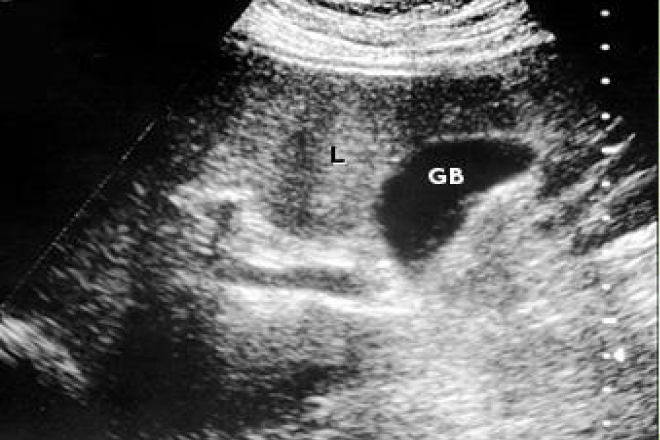

Otra forma de encontrar la enfermedad es el aumento de la ecogenicidad hepática en una ecografía abdominal muchas veces indicada por otras causas. Dependiendo del grado de afectación, podría acompañarse de signos ecográficos de hepatopatía crónica.